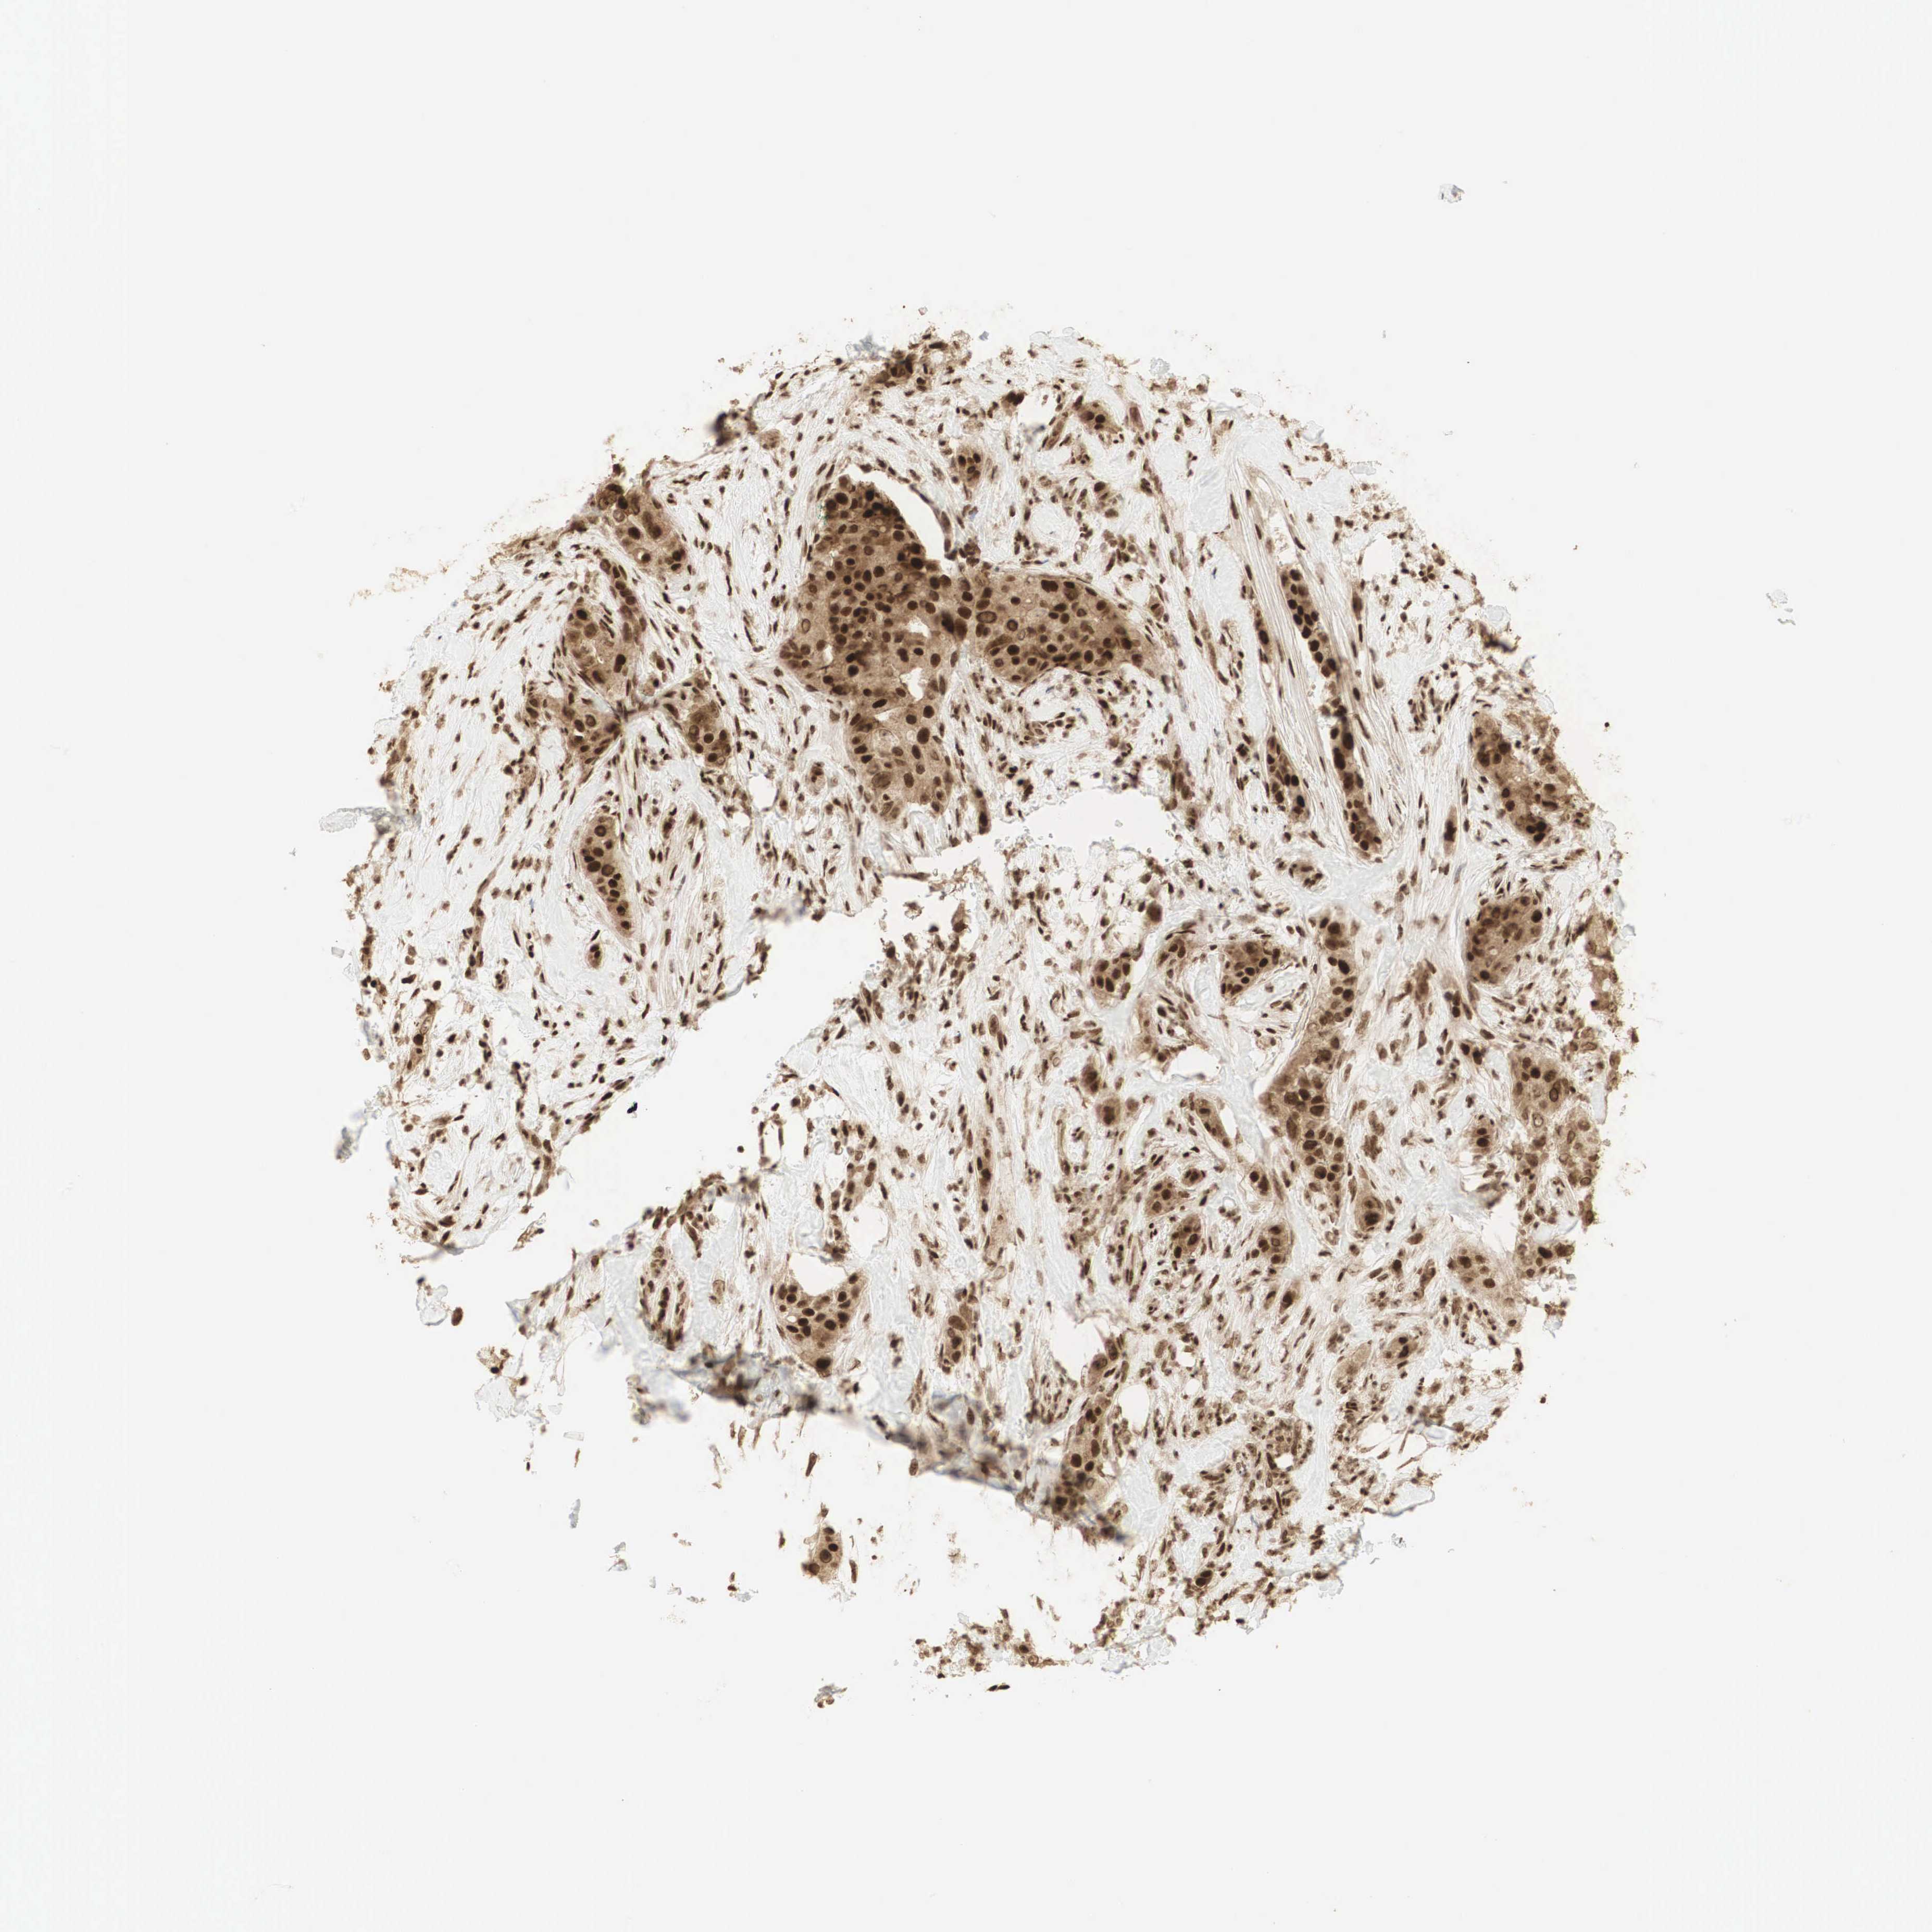

CANCER BREAST CANCER Show tissue menu

BRCA TCGA BRCA VALIDATION PROTEIN EXPRESSION